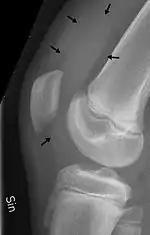

| Traumatic effusion of the right knee, with swelling lateral to the kneecap marked by an arrow | |

Knee effusion, informally known as water on the knee, occurs when excess synovial fluid accumulates in or around the knee joint. It has many common causes, including arthritis, injury to the ligaments or meniscus, or fluid collecting in the bursa, a condition known as prepatellar bursitis.